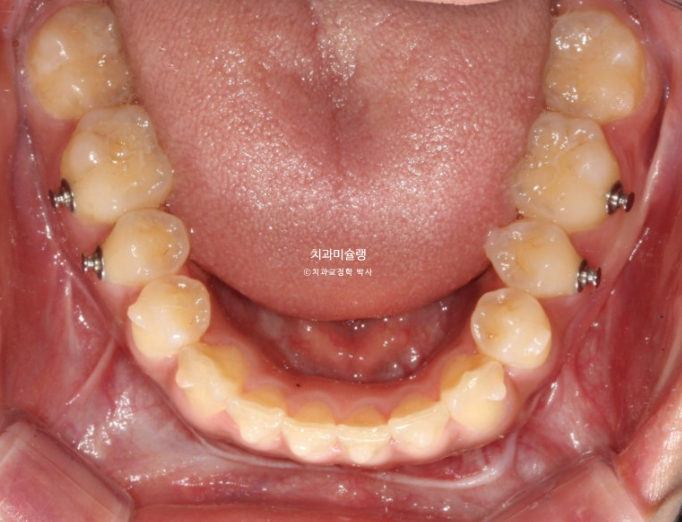

중심선은 정확히 맞으며

어금니 교합은 물샐틈 없는 1급 교합관계를 보입니다.

이제 교합 전후비교 보겠습니다.

25.02~25.10

치근흡수는 없으며 치근평행도는 양호합니다.